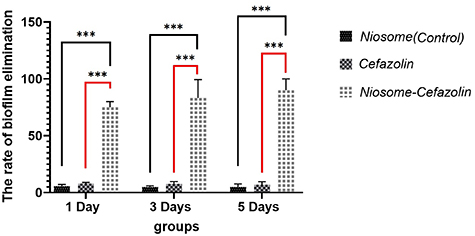

2.4.7. Minimal biofilm eradication concentration (MBEC)

MBEC was carried out to evaluate the efficacy of cefazolin-containing niosome against MRSA biofilm. MRSA isolates were cultured on solid agar. Twenty microliters of serially diluted bacterial suspensions (108 CFU ml−1) was added to the wells of three sterile 96-well microtiter plates which were filled with 180 µl per well of TSB medium (Merck, USA) supplemented with 1% glucose in advance. The plates were incubated for 1 d, 3 d, and 3 d in separate groups at 37 °C. The wells were washed with 200 µl of sterile saline to remove the non-adherent cells. Hundred microliters of cation-adjusted nutrient broth was added to each well followed by 100 µl of cefazolin-containing niosome except for the control wells. The plates were incubated for 24 h at 37 °C and rinsed three times with sterile saline. The wells then were stained using a 2,3,5-triphenyl-tetrazolium chloride method [35]. The plates were read with an automated ELISA reader (Titertek, R Multiscan) at wavelength 470 nm.

3.6. Minimal biofilm eradication concentration (MBEC)

The results of MBEC showed that cefazolin only inhibited S. aureus isolates in the 1 d old plate at the concentration of 256 µg ml−1 and had no inhibition effect on MRSA. Cefazolin-loaded niosome inhibited biofilm formation of both MRSA and S. aureus isolate at the concentration of 128 µg ml−1 and 64 µg ml−1, respectively (Table 2). In the 3 d old group, the MBEC of cefazolin-loaded niosome was 128 µg ml−1 for both MRSA and S. aureus. Cefazolin-loaded niosome inhibited biofilm formation of MRSA and S. aureus at the concentrations 256 µg ml−1 and 128 µg ml−1, respectively in a 5 d old plate. The elimination rate of cefazolin, cefazolin-loaded, and non-leaded niosomes on biofilm formation of MRSA and S. aureus isolates in 1 d, 3 d, and 5 d old plates are shown in figure 6.

Figure 6. Comparison of elimination rate of cefazolin, cefazolin-loaded and nonleaded niosomes against 1 d, 3 d and 5 d old biofilm of MRSA and S. aureus isolates. Cefazolin-loaded niosomes showed definitely higher biofilm elimination rate in all three plates. P-value < 0.0001.

The results indicate the successful anti-biofilm capability of our cefazolin-load niosomes. The results of the MBEC assay showed no elimination effect against MRSA biofilms. However, cefazolin-loaded niosomes had a significantly higher biofilm elimination rate for both S. aureus and MRSA in all plates compared to other groups. The highest biofilm elimination rate of cefazolin-loaded niosomes was observed in 1 d old wells inoculated by both S. aureus and MRSA isolates. It is implied that niosomes containing antibiotics fused with the biofilm matrix and successfully transferred unchanged antibiotics to accumulated bacterial cells and improved drug penetration. The anti-biofilm effect of cefazolin-loaded niosomes was stably maintained in a 5 d old plate which suggests the appropriate efficacy of our niosomes in chronic exposure to the site of colonization which can lead to fewer drug usage and intake intervals. Also, the results of CLSM analysis showed a significant reduction of biofilm density and bacterial counts in niosomal cefazolin-treated coverslip.